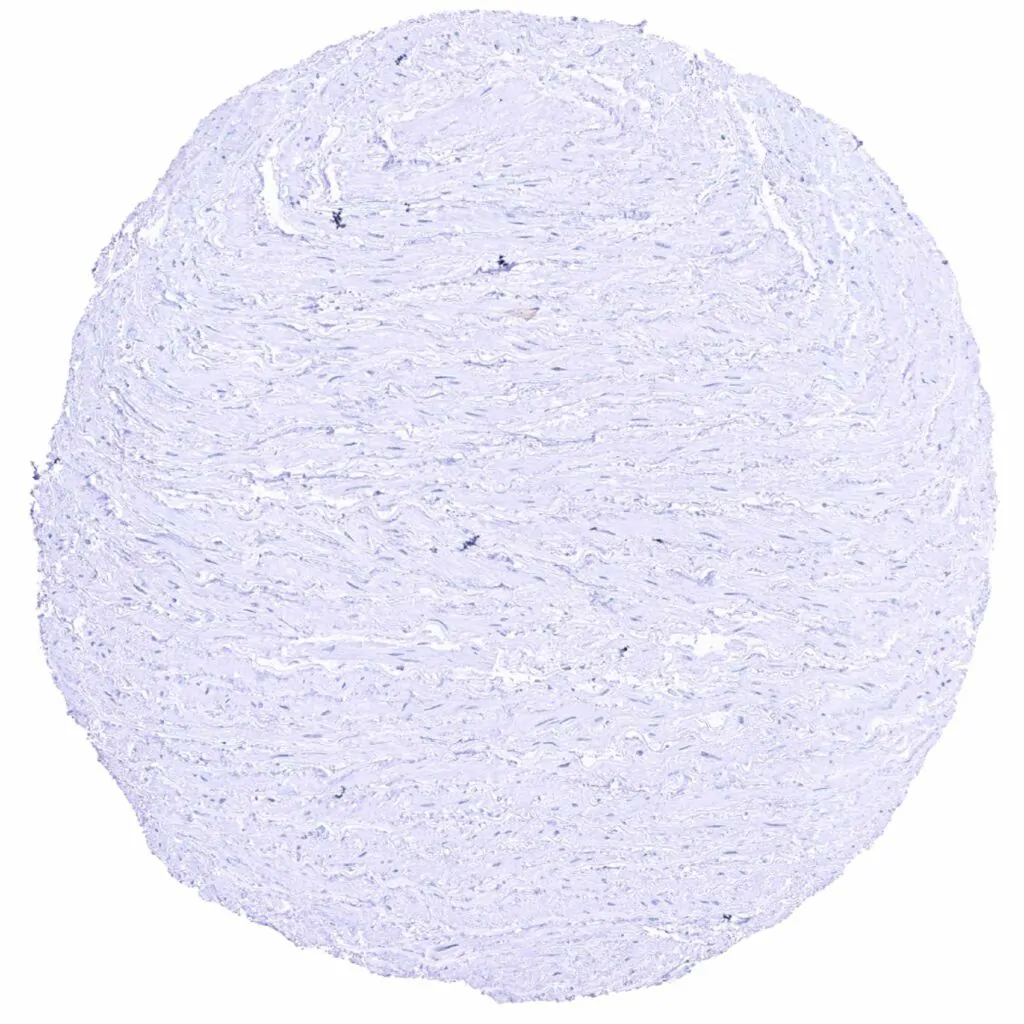

Fat